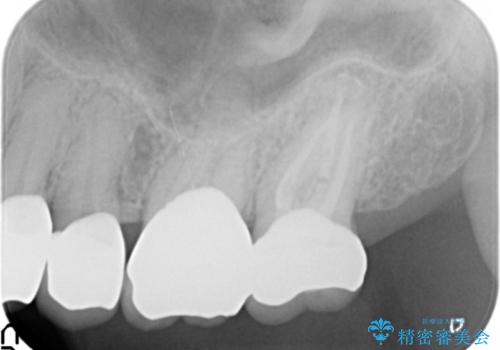

- 左上の一番奥の歯の根の治療を行いつつ、手前の歯の被せ物のやり直しも一緒に行いました。

- 約70万円 内訳:ジルコニアクラウン10万円x4、TeC 1万円x4 根管治療15万円、ファイバーコア2万円費用は治療当時の料金となります

根の治療は当法人の根管治療の認定医である林先生にお願いしました。